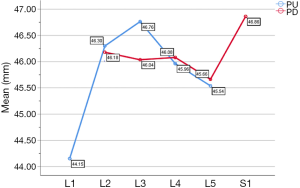

In the medium group, PC path was the shortest (38.56±3.25 mm), PA path and PB path had little difference (P=0.123), and there was no statistical significance. In the full-length group, PF path was the shortest (43.86±3.09 mm), and there was no significant difference between PD path and PE path (P=0.177) (Figure 10). All the paths increased successively from L1 to S1, among which PA and PD paths were the most obvious, followed by PB and PE paths. PC path and PF path first increased and then decreased (Figures 11,12).

The included angles a1, a2, a3, b1, b2, b3 and c1, c2 and c3 in the sagittal plane were significantly different (P≤0.001) (Figure 13) (a1 > a2 > a3, b1 > b2 > b3, c1 < c2 < c3). In the angles of sagittal down-path, b1, b2 and b3 change significantly and consistently, showing a trend of decreasing first and then increasing, which is the smallest at L3 (46.08±4.37°, 36.21±3.51°, 22.47±3.01°) and the largest at S1 (69.49±8.28°, 61.23±7.74°, 36.60±5.00°). In the angles of sagittal up-path, a1 and a2 change in the same way, showing an increasing trend. While a3 goes down and then goes up, which is the smallest at L4 (23.43±4.29°) and the largest at L5 (24.36±2.94°). In the angles of axial plane, c1, c2 and c3 change in the same way, showing a trend of increasing first and then decreasing. c1 and c2 are the largest at L2 (40.07±2.75°, 55.1±3.32°), and c3 is the largest at L3 (73.11±2.10°). c1, c2 and c3 are the smallest at S1 (33.87±2.94°, 47.92±3.54°, 67.15±3.60°) (Figures 14,15).

PE path was the longest in all the paths for oblique fixation from posterior corner in lumbar spine, with an average length of 45.95 mm, which was significantly longer than other paths in the same vertebral body (Figures 10-12). Its upward path first increases and then decreases, reaching the highest point at L3 (46.76±2.88 mm). Its downward path first decreases and then increases, with the lowest decline at L5 (45.66±3.21 mm) (Figure 20). At the same time, the fixed angles (a2, b2, c2) of the PE path in sagittal and axial planes are between a1-a3, b1-b3, and c1-c3, which may neither penetrate into the intervertebral space nor injure the anterior large vessels. Therefore, the PE path is safe and easy to grasp in theory.